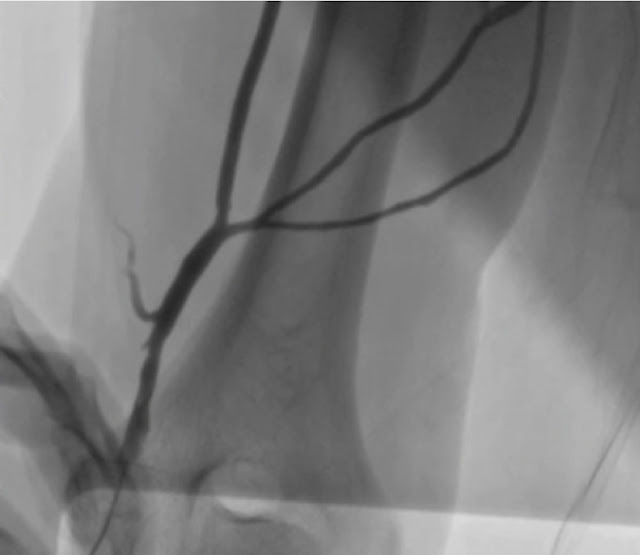

All 64 procedures were successful with no serious complications. Fifty-six from 64 procedures (87.5%) were successfully performed via AVA. Mean diameter of antecubital and basilica veins measured by ultrasound were 3.5±0.9mm and 4.1±1.5mm. In 8 cases (12.5%) we failed to perform AVA due to the following reasons: diameter of the vein was less than 2 mm (n=3), difficulties in placement of Braunul micro-catheter (n=1), vascular abnormalities (n=3) (Figure 2), vein perforation with extravasation (n=1). Local extravasates were treated with bandage compression. There were no other complications via AVA. These procedures (n=8) were succefully performed via femoral vein access. Maximum amount of procedures performed through the same antecubital vein was 6. In average, there were 2.6±1.6 procedures per one antecubital vein in all 19 patients (Table 1).

Figure 2. Vascular abnormalities of v. basilica.